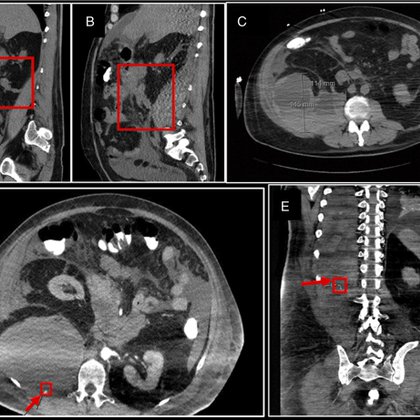

Congratulations to @akashkhurana_ for publishing this unique complication of necrotizing pancreatitis 👏 @UH_RE_Institute @CWRU_GI @AmCollegeGastro @ACGCRJ @BrookeGlessing Lumbar Artery Pseudoaneurysms Presenting as a Novel... : ACG Case Reports Journal

tis. A 55-year-old man initially presented with necrotizing biliary pancreatitis complicated by peripancreatic necrotic fluid collections and walled-off necrosis requiring multiple endoscopic...

Happening now!! Alert alert ‼️ Come check out our case report on the first occurrence of lumbar artery pseudoaneurysms as a direct complication of severe, necrotizing pancreatitis @BrookeGlessing @akashkhurana_ @AmerGastroAssn @DDWMeeting @CWRUdeptMED Poster 1037 at #DDW2023!